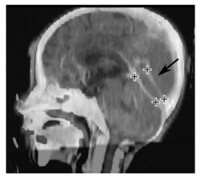

Head1.png Head2.png

We are introducing a new method for local enhancement of image registration. The method is intended to make rapid, interactive corrections of local registration failures with a small number of mouse clicks. We use Gaussian radial basis functions (RBFs) to define a vector field from point landmarks, and apply regularization based on the vector field second order derivative.

Our approach is based on the fact that the Gaussian RBF has infinite support, but the influence of each RBF is localized, making this method well suited for local corrections. In addition, Gaussian RBFs have a distinct advantage over competing approaches such as Wendland functions, because the regularized vector field can be solved exactly with a simple equation. Algorithm for the landmark-based registration has been implemented as a part of out in-house software Plastimatch. We have validated the method on 10 large landmark sets. This work has been submitted for publication to IEEE Transactions on Medical Imaging.